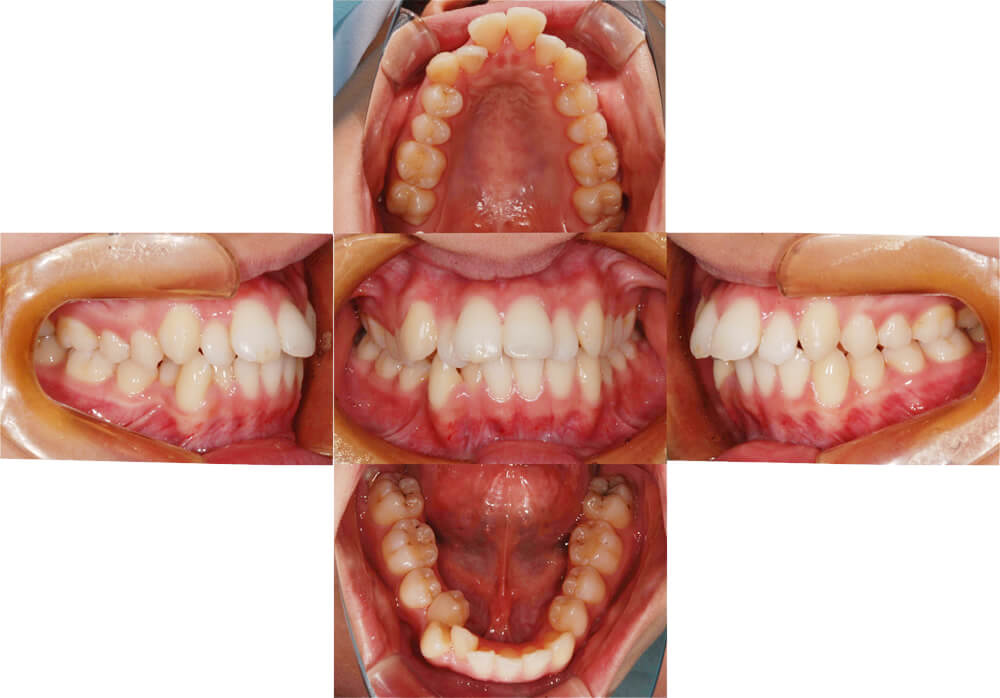

症例1

| 主訴 | 前歯が噛まない |

|---|---|

| 診断名 | 叢生を伴う開咬症例 |

| 年齢 | 25歳 |

| 装置 | マルチブラケット装置 |

| 抜歯部位 | 上下左右第一小臼歯 |

| 治療期間 | 2年半の動的治療期間 |

| 治療費 | 800,000〜1,000,000円 |

| リスク・副作用 | 歯肉退縮、歯根吸収、疼痛、口内炎、歯ブラシが大変、骨性癒着、見た目、抜歯の可能性、毎月来院が必要、治療期間が長い |